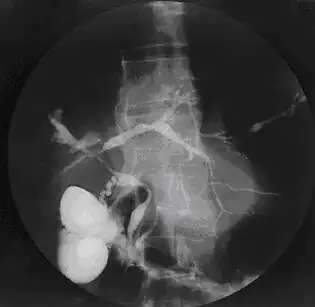

| Colangiograma na CEP | |

A colangite esclerosante primária (CEP) é uma doença crônica do fígado causada pela inflamação e cicatrização progressivas das vias biliares intra-hepáticas e extra-hepáticas.

O processo inflamatório provoca estreitamentos (estenoses) da via biliar, o que impede a adequada circulação da bile para o intestino. A doença com frequência evolui para cirrose, insuficiência e carcinoma hepáticos, como consequência do potencial inflamatório da bile, que é rica em sais biliares hidrofóbicos e citotóxicos (danosos às células do fígado).